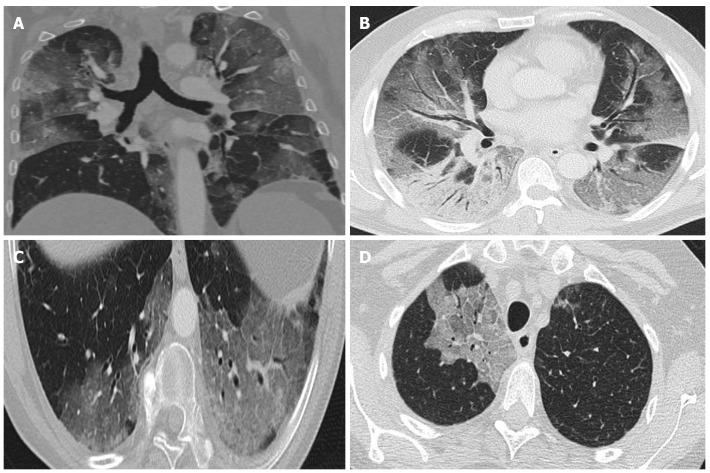

Coronavirus disease 2019 (COVID-19) was discovered after unusual cases of severe pneumonia emerged in December 2019 in Wuhan Province (China). Coronavirus is a family of single-stranded RNA viruses. Severe acute respiratory syndrome coronavirus 2 (SARS-CoV-2) is transmitted from person to person. Although asymptomatic individuals can transmit the virus, symptomatic patients are more contagious. The incubation period ranges from 3-7 d and symptoms are mainly respiratory, including pneumonia or pulmonary embolism in severe cases. Elevated serum levels of interleukins (IL)-2, IL-6, IL-7 indicate the presence of cytokine release syndrome, which is associated with disease severity. The disease has three main phases: Viral infection, pulmonary involvement, and hyperinflammation. To date, no treatment has proved to be safe or effective. Chest X-ray and computed tomography (CT) are the primary imaging tests for diagnosis of SARS-CoV-2 pneumonia, follow-up, and detection of complications. The main radiological findings are ground-glass opacification and areas of consolidation. The long-term clinical course is unknown, although some patients may develop pulmonary fibrosis. Positron emission tomography-computed tomography (PET-CT) is useful to assess pulmonary involvement, to define the affected areas, and to assess treatment response. The pathophysiology and clinical course of COVID-19 infection remain poorly understood. However, patterns detected on CT and PET-CT may help to diagnose and guide treatment. In this mini review, we analyze the clinical manifestations and radiological findings of COVID-19 infection.

2019年12月,中国湖北省武汉市出现异常严重肺炎病例后,2019冠状病毒病(COVID-19)被发现。冠状病毒是一类单链RNA病毒。严重急性呼吸综合征冠状病毒2(SARS-CoV-2)可人际传播。虽然无症状个体也可传播病毒,但有症状的患者传染性更强。潜伏期为3至7天,症状主要为呼吸道症状,严重时包括肺炎或肺栓塞。血清白细胞介素(IL)-2、IL-6、IL-7水平升高表明存在细胞因子释放综合征,这与疾病严重程度相关。该疾病有三个主要阶段:病毒感染、肺部受累和过度炎症。迄今为止,尚无治疗方法被证明是安全有效的。胸部X线和计算机断层扫描(CT)是诊断SARS-CoV-2肺炎、进行随访及检测并发症的主要影像学检查。主要影像学表现为磨玻璃样混浊和实变区域。尽管一些患者可能会发展为肺纤维化,但长期临床病程尚不清楚。正电子发射断层扫描-计算机断层扫描(PET-CT)有助于评估肺部受累情况、确定受累区域及评估治疗反应。COVID-19感染的病理生理学和临床病程仍知之甚少。然而,CT和PET-CT上检测到的模式可能有助于诊断和指导治疗。在本综述中,我们分析了COVID-19感染的临床表现和影像学表现。